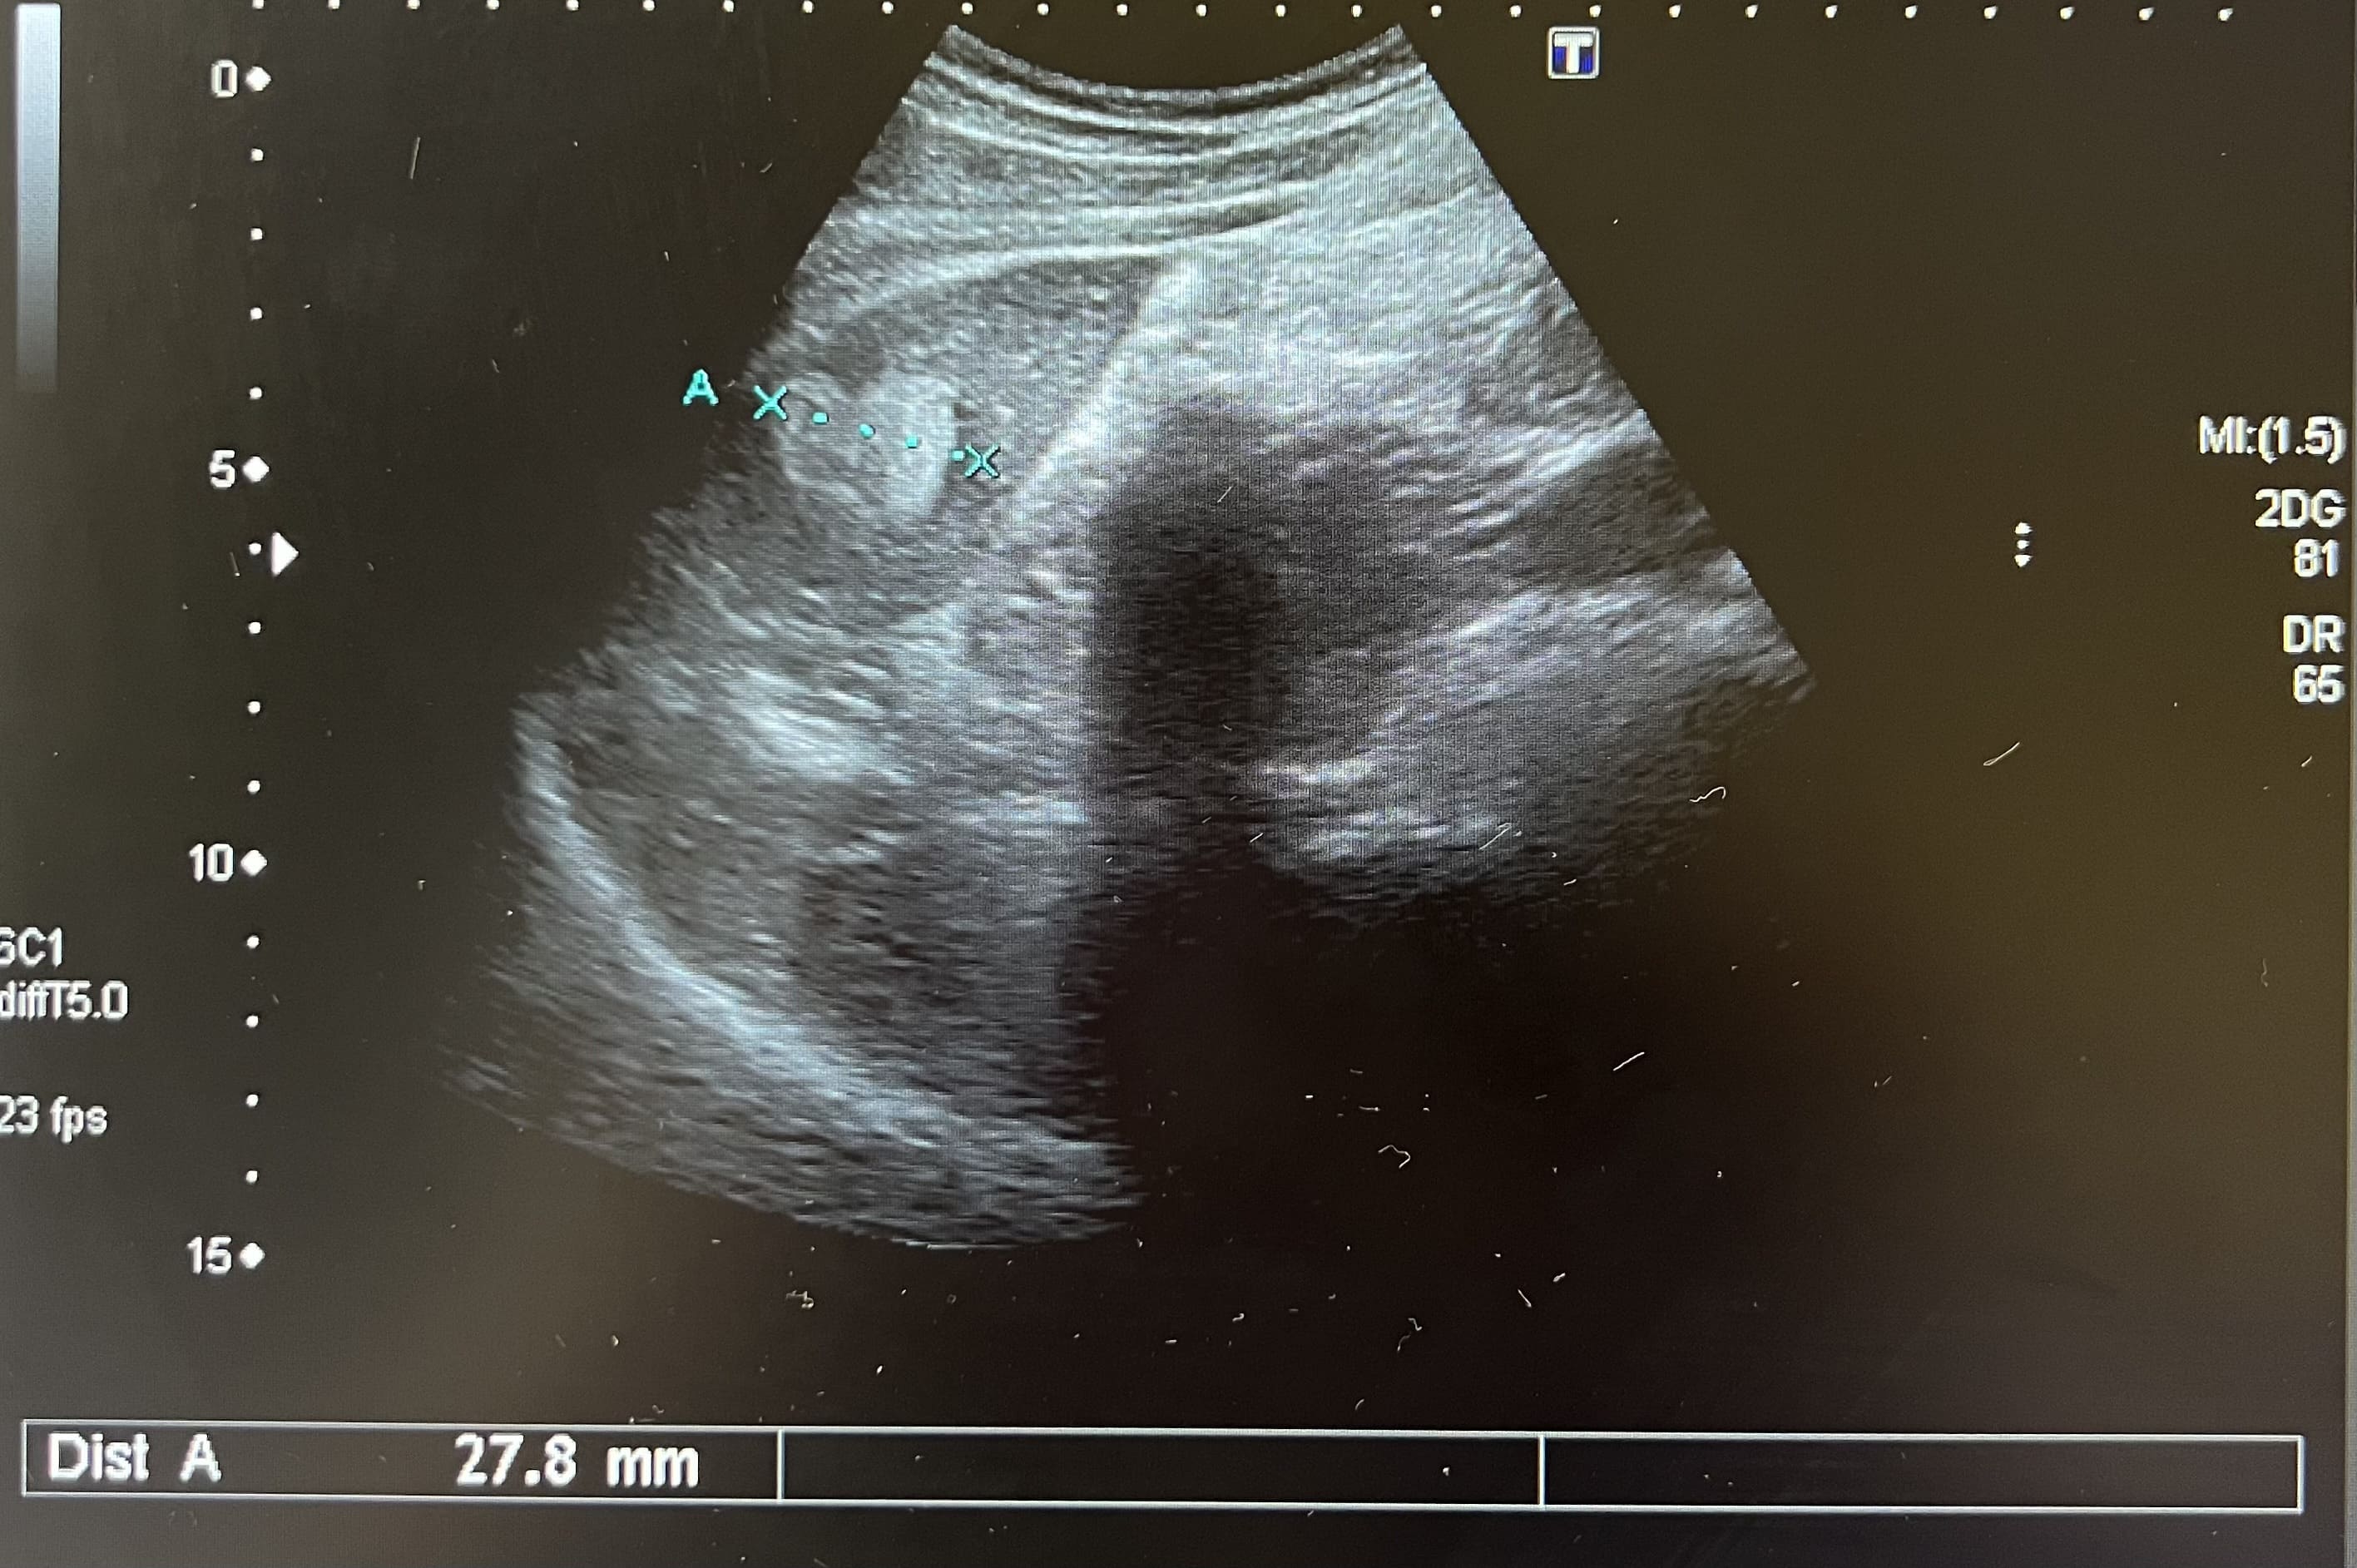

Pruebas complementarias: analítica normal. La ecografía abdominal muestra múltiples imágenes ecogénicas bien definidas en ambos lóbulos, de tamaño variable. Vesícula biliar con dos litiasis subcentimétricas y discreto edema de pared compatible con colecistitis. Estos hallazgos se confirman mediante la realización de una ecografía reglada por parte de radiología.

Juicio clínico: Hemangiomas hepáticos. Colecistitis.

Diagnóstico diferencial: con otras lesiones focales sólidas del hígado. La imagen ecográfica del hemangioma es de una o varias lesiones hiperecogénicas bien definidas que no captan Doppler. La hiperplasia nodular focal se presenta como una lesión hipo o isoecoica que puede captar Doppler. El adenoma se presenta como una masa hiper o hipoecoica con áreas anecoicas, mostrando el Doppler un tumor hipervascular. El hepatocarcinoma tiene un aspecto ecográfico variable, como masa o nódulos hipoecoicos, mal diferenciados e hipervascularizados. Las metástasis hepáticas se suelen presentar como múltiples lesiones sólidas de tamaño y ecogenicidad variables y la presencia de un halo hipoecoico rodeando la masa.

El hemangioma hepático es el tumor hepático benigno más frecuente, con mayor prevalencia en mujeres. Se suelen presentar en forma de lesión única, aunque pueden aparecer en forma de lesiones múltiples, con un tamaño normalmente inferior a 30 milímetros. Suele ser un hallazgo casual, al ser asintomáticos. El diagnóstico diferencial se realiza con otras lesiones hepáticas sólidas y se recomienda un seguimiento ecográfico para confirmar estabilidad.